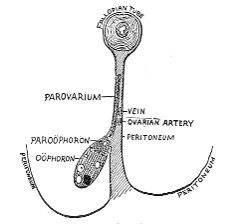

The origin of vaginal cysts has been much disputed. It is probable that they arise from the remains of the Wolffian canal—the canal of Gärtner. In the embryo the transverse or longitudinal tubule of the parovarium extends to the side of the uterus and thence down the side of the vagina to the urethral orifice. It persists in this condition in some of the lower animals—the sow and the cow—and may also persist as a closed tube in woman. In such cases it may become distended and form the vaginal cyst.